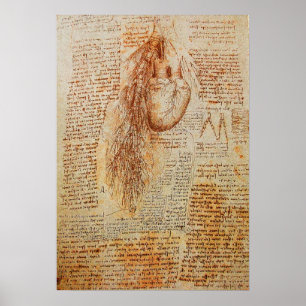

Póster O coração e as artérias bronquiais

Preço80,00 €